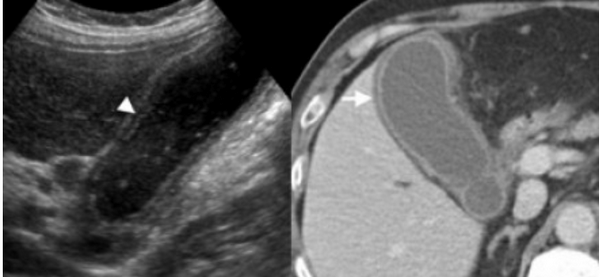

(Слева) На аксиальной КТ с контрастным усилением у женщины 64 лет с хронической болью в правом подреберье определяется утолщение стенки желчного пузыря и гиподенсные включения в ней. При патоморфологическом исследовании было обнаружено, что эти гиподенсные включения представляют собой зоны некроза, заполненные пенистыми макрофагами. Обратите внимание на усиление перфузии печени (преходящее повышение плотности).

(Справа) На сонограмме у этой же пациентки определяется утолщение стенок желчного пузыря, просвет которого заполнен сладжем, с наличием множественных кистозных участков некроза в передней стенке.

УЗИ и КТ желчного пузыря. Ксантогранулематозный холецистит. Слева на УЗИ визуализируется (помечено стрелками) утолщение стенки желчного пузыря с интрамуральным включением и с камнем в просвете органа. Справа на КТ выявляется утолщение стенки с гиподенсными включениями.

Выше представлено КТ пациента 71 года с ксантогранулематозным холециститом. Постконтрастное КТ. Визуализируется утолщение стенки желчного пузыря с включениями, которые соответствуют абсцессу или фокусам воспаления.